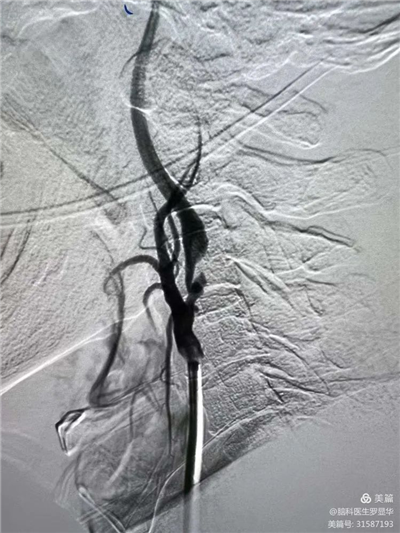

沈桂冬主任團(tuán)隊(duì)正在為患者行PCI術(shù) Xbg安康新聞網(wǎng)

冠脈造影證實(shí)左旋支重度狹窄Xbg安康新聞網(wǎng)

釋放冠脈球擴(kuò)支架Xbg安康新聞網(wǎng)

支架植入后狹窄完全解除Xbg安康新聞網(wǎng)